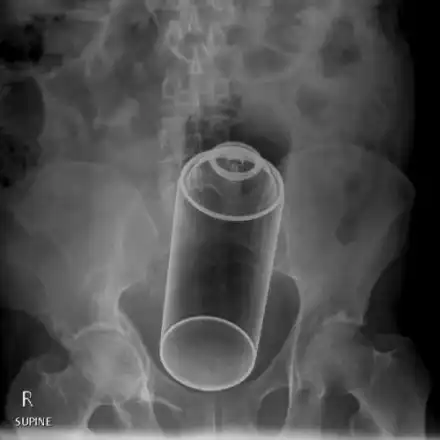

Лекари от „Пирогов“ извадиха дезодорант от д*пето на 14-годишно момче

По спешност в „Пирогов“, със заврян дезодорант в задните части, се оказа 14-годишен младеж. Историята на малкия палавник се разиграла...